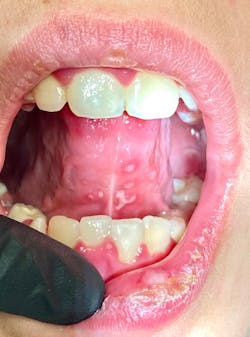

This 12-year-old presented with his mom for a dental visit. The chief complaint was that he was not feeling well, his mouth hurt, he couldn’t eat, it was painful to swallow, and he’d missed out on the last week of school. In general, his health history was unremarkable, temp was low-grade (99.8), and despite not being 100%, he was a trouper. Fist bumps, kiddo.

Note: The pictures are not of the highest quality as the patient was in extreme discomfort when I took them.

Definitive diagnosis is likely one of two: Herpangina or acute primary herpetic gingivostomatitis

The saying “nothing is for certain unless it’s in a petri dish” stands true in all pathology cases, including this one. However, based on the symptoms and clinical presentation, I was able to surmise that it was more than likely either herpangina or APHG, although I’m leaning toward APHG.

For my patient, I prescribed Magic mouthwash, told him to rest (mom was on board with that), keep his oral cavity as clean as possible (several of my patients have found a diluted Listerine or chlorhexidine rinse to be helpful, but not all can tolerate it), and let it run its course. Mom was to contact me if it didn’t start to improve or get better after 10–14 days.